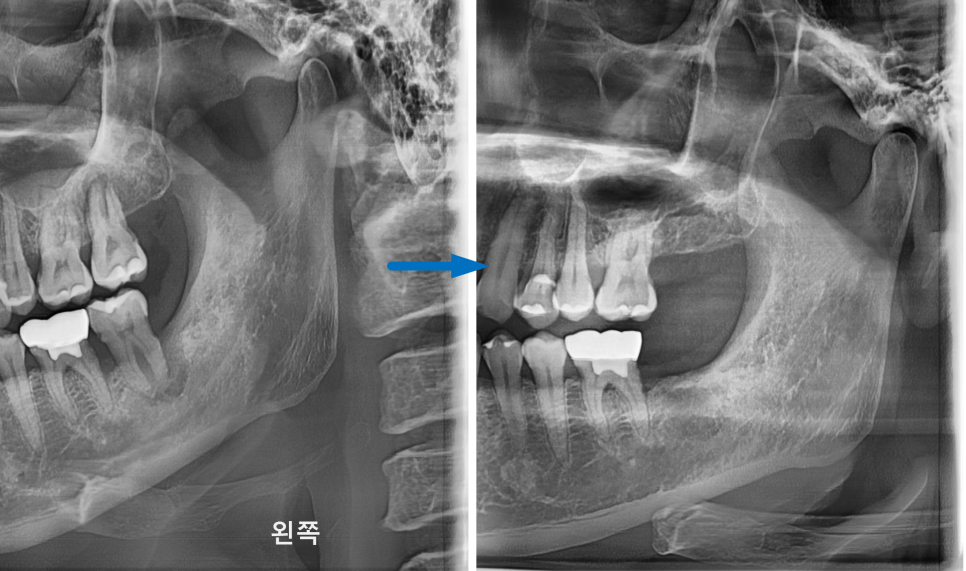

그 이유는 이 환자분의 경우 상악동거상술이 같이 동반되어야 하는 경우로

상악동과의 치조골 높이를 측정하였을 때

왼쪽 위 치아가 오른쪽 치아보다 잔존골 높이가 낮아

상악동거상술을 더 많이 해야 하고

더 오래 기다려야 하기 때문이였는데요.

양쪽으로 한 번에 식립하게 되면

환자분이 너무 힘들 수 있기 때문에 위와 같은 이유로

오른쪽 먼저 진행하시기로 하셨습니다.

상악동에 대해서 좀 더 설명드리겠습니다.

상아공이란 두개골과 코 사이에 위치한 빈 공간을 말합니다.

위턱에 임플란트를 심을 경우 상악동도 꼭 같이 정밀체크합니다.

상악동이 크고 뼈의 두께가 얇은 경우, 아래로 내려온 상악동을

위로 올려 임플란트 식립 공간을 충분히 확보해 줘야 합니다.

이 시술을 상악동 거상술이라고 합니다.